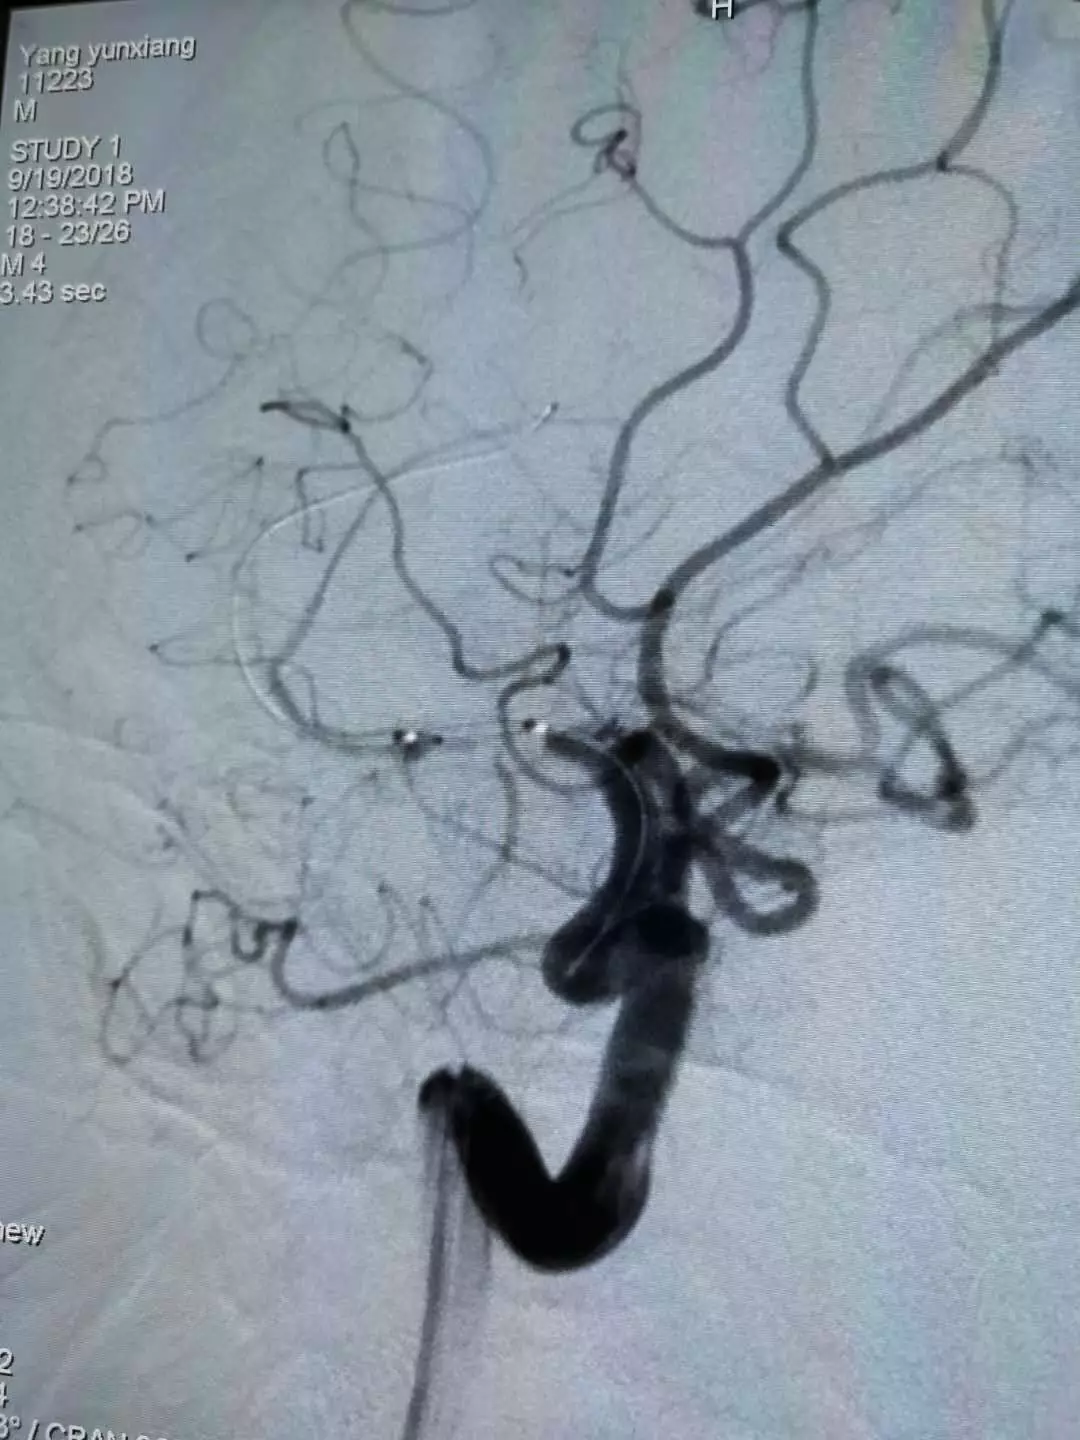

造影及诊断

诊断:

1、右侧大脑中动脉闭塞;

2、脑梗塞;

3、不完全性偏瘫。

治疗中造影(点击可查看大图)

微导管造影1

微导管造影2

微导管造影3